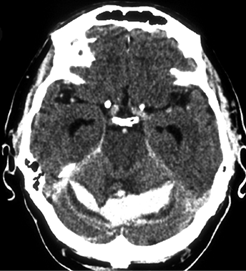

Субарахноидальные кровоизлияния классифицируют по этиологическому фактору (см. выше) и по распространенности на основании данных КТ или МРТ. При этом учитывают как массивность кровоизлияния, так и его сочетание с другими компонентами внутричерепного кровоизлияния — паренхиматозным и вентрикулярным. В зависимости от этого фактора выделяют изолированное субарахноидальное кровоизлияние, субарахноидально-паренхиматозное, субарахноидально-вентрикулярное и субарахноидально-паренхиматозно-вентрикулярное кровоизлияния (рис. 12.6). В мировой практике широкое распространение получила классификация субарахноидальных кровоизлияний, предложенная M. Fisher (1980). Она характеризует распространенность субарахноидального кровоизлияния по результатам КТ (табл. 12.1).

img96

Рис. 12.6. Типичное субарахноидальное кровоизлияние. Видно симметричное распространение крови в базальных цистернах, межполушарной щели, конвекситальных субарахноидальных пространствах (компьютерная томограмма)